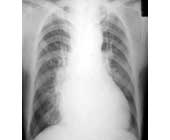

右心聲學造影系從周圍靜脈注入聲學造影劑。使右心繫統顯影,包括上下腔靜脈、右心房右心室及肺動脈。用以顯示右心繫統各腔室的解剖結構和血流狀況,診斷右(左分流的先天性心臟病和瓣膜的返流。

右心造影最大優點在於造影劑集中,心臟大血管的影像不互相重疊,故顯影效果滿意。若能同時結合心導管檢查的資料,則更能提高診斷的準確性。

可作以下心血管疾病的診斷:(1)先天性心臟病術前明確診斷;(2)確定心臟雜音的性質,以便指導治療;(3)心臟手術後再度出現症狀,需再行手術者。